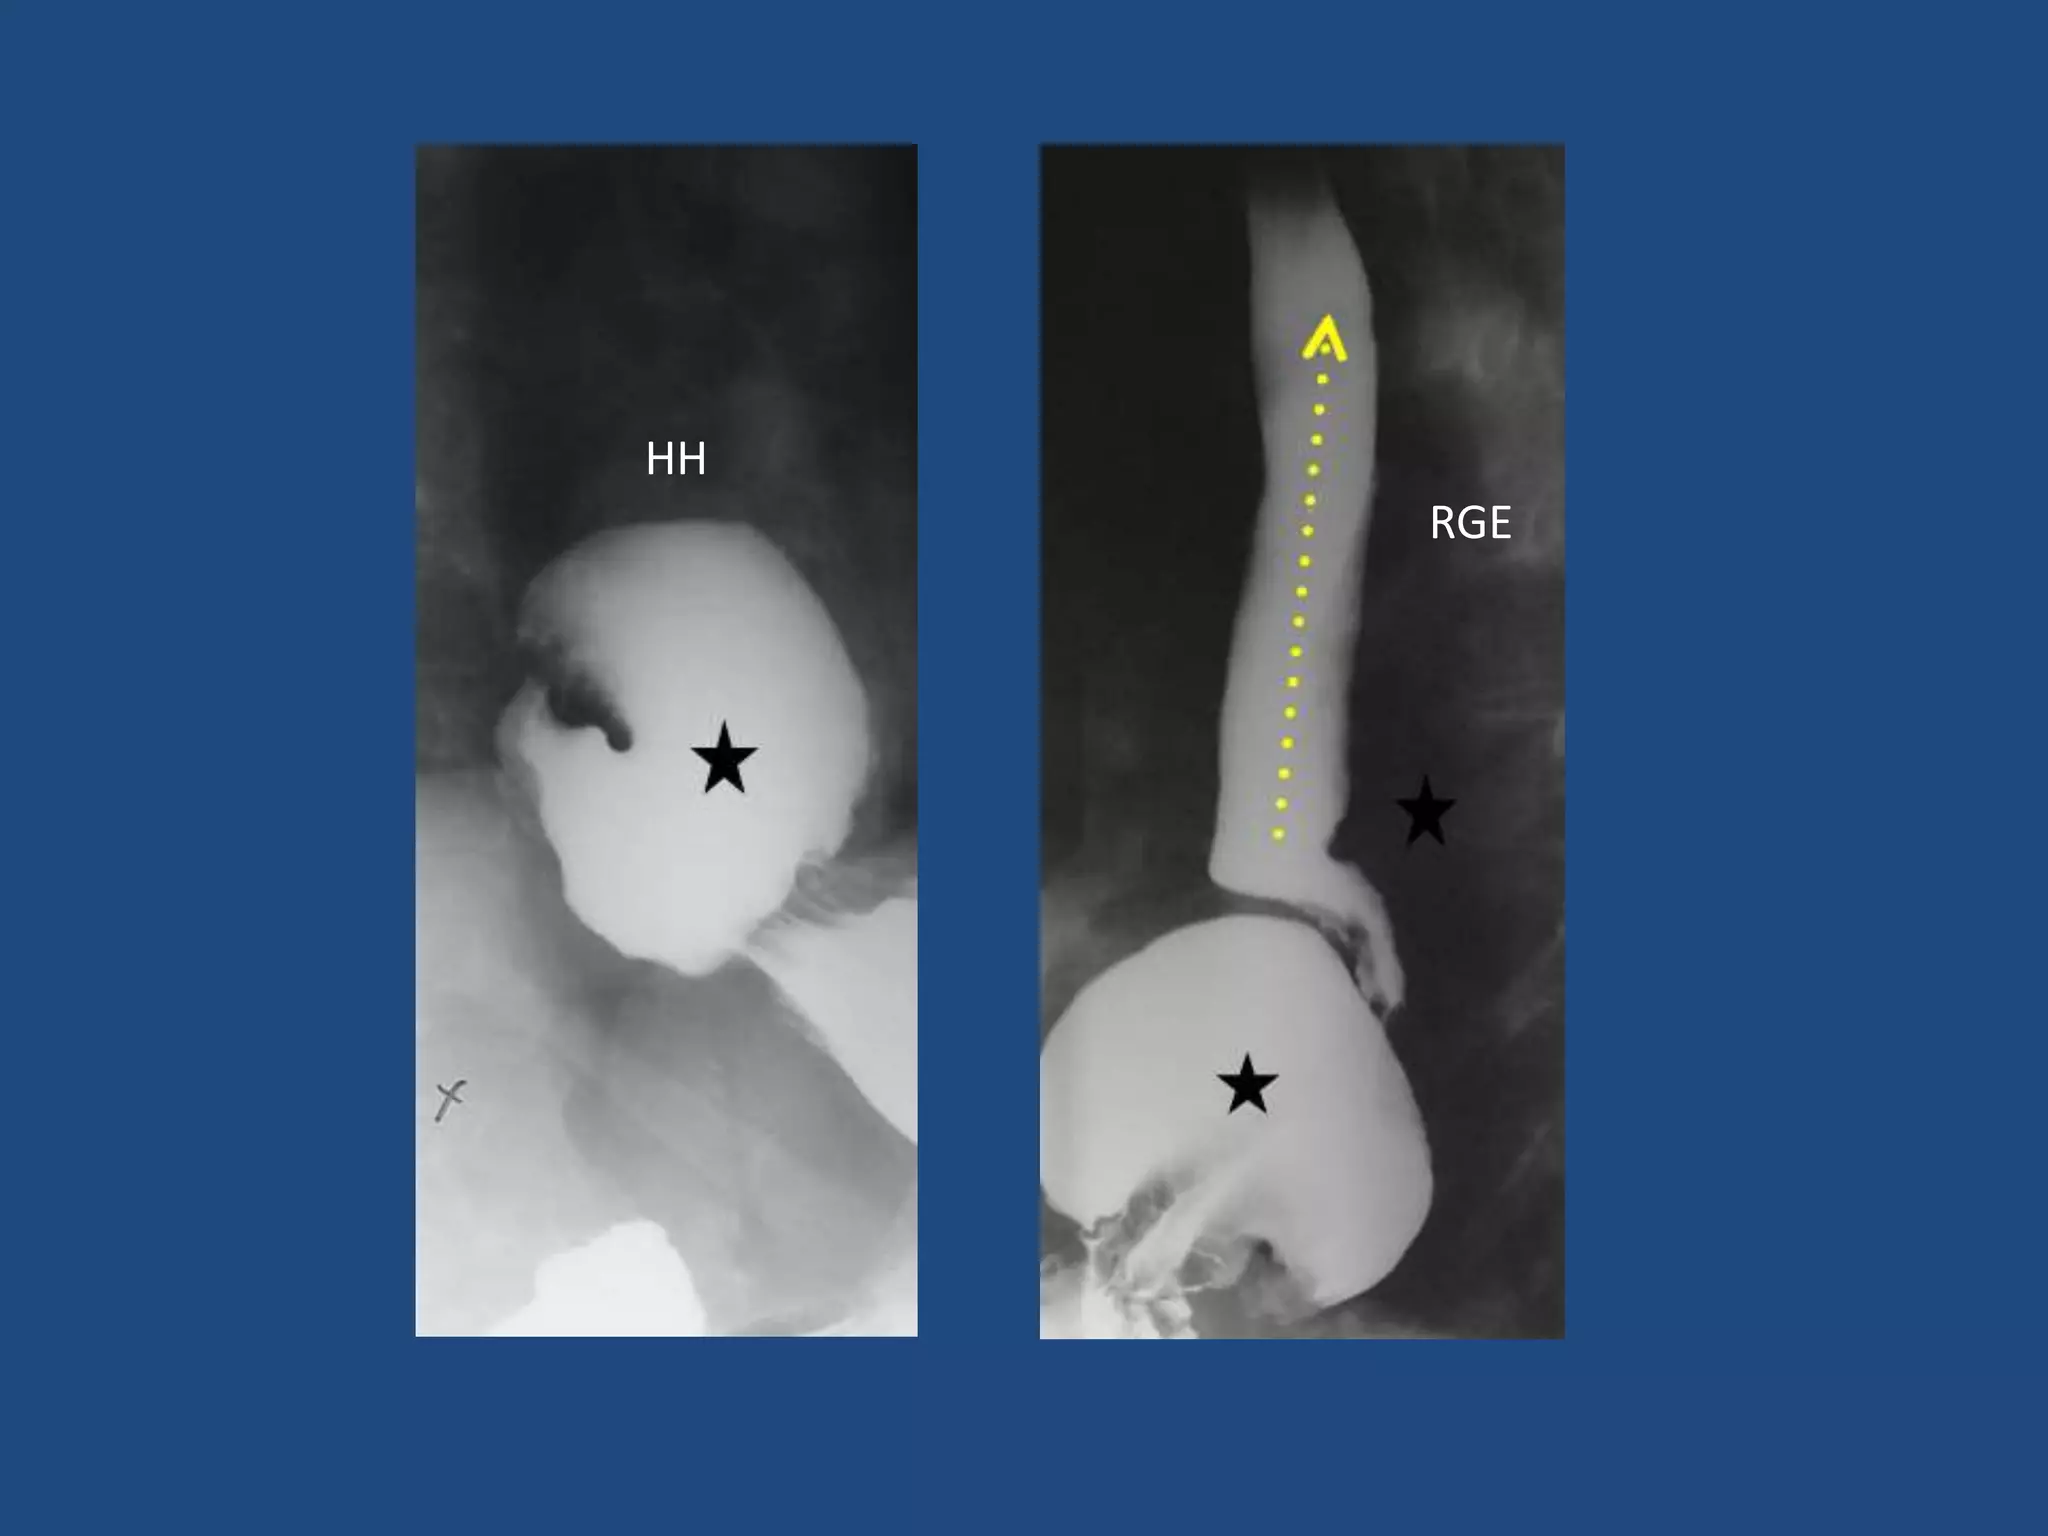

ESOFAGO: HERNIA HIATAL

• Ascenso parcial o total del estomago al tórax

• Principal factor predisponente de RGE

• Hallazgo :

- Ascenso visceral

HH

RGE